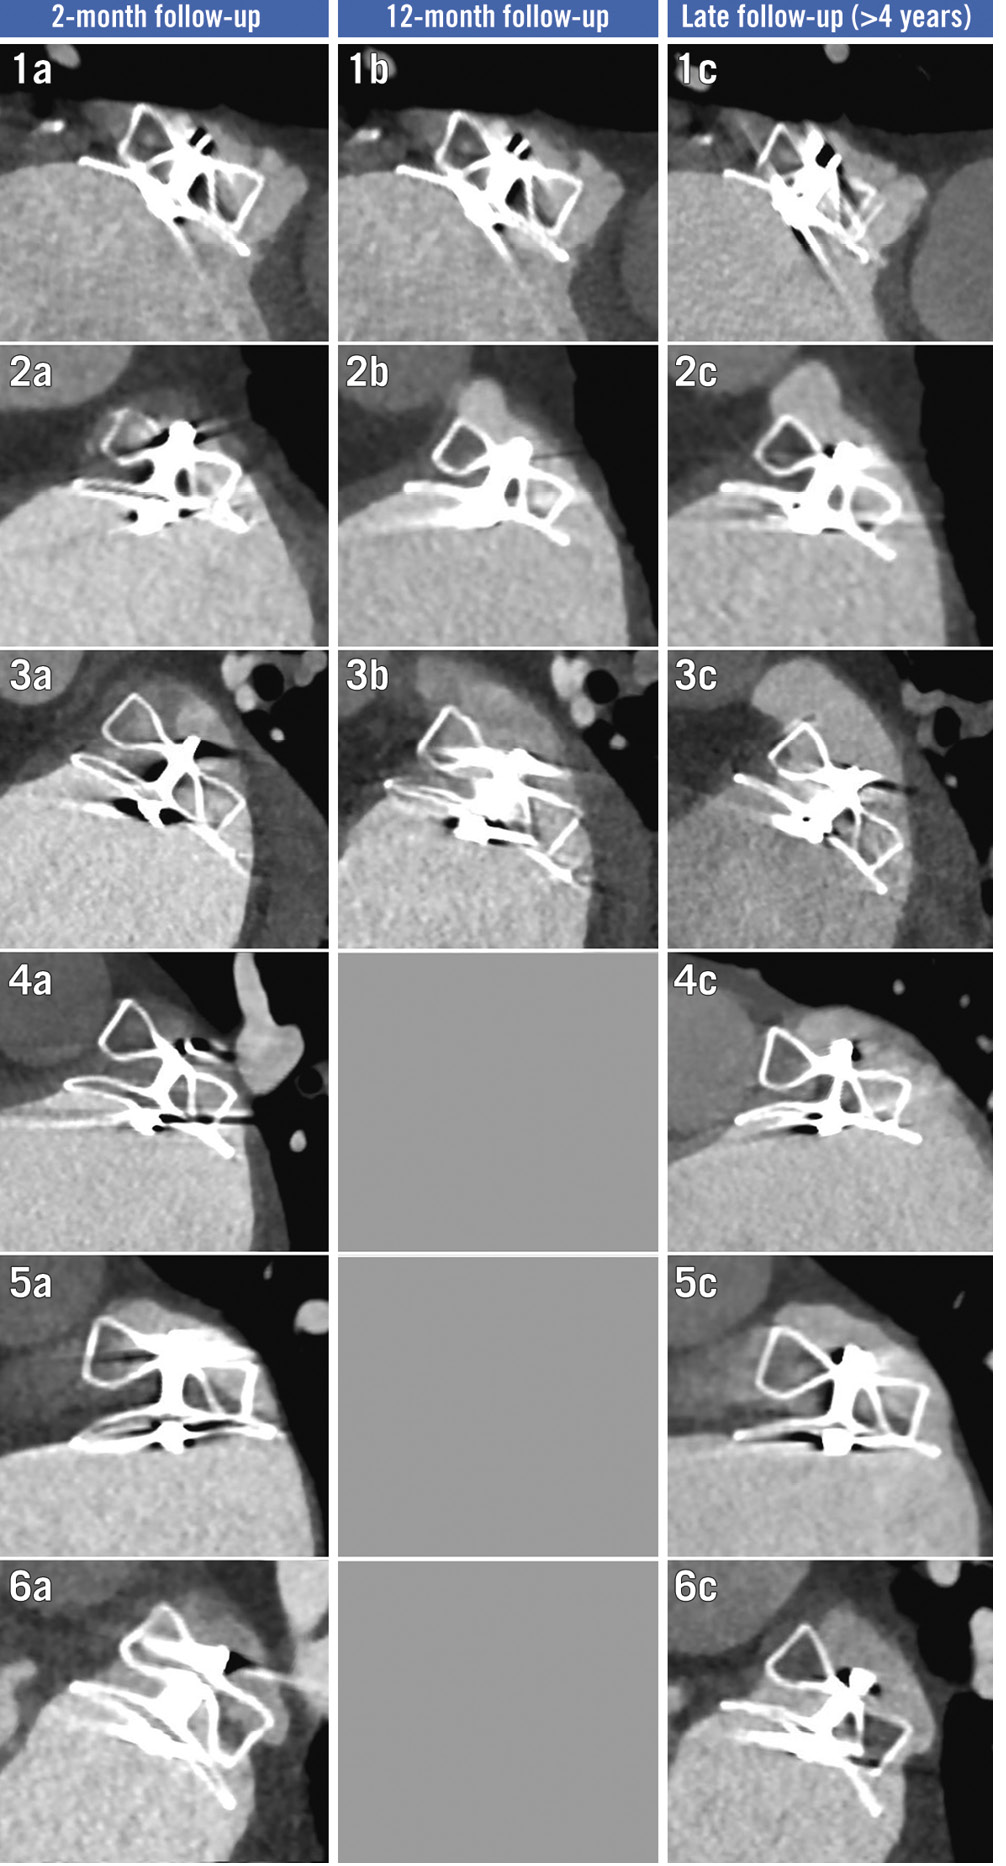

Figure 3. Temporal evolution of six grade 3 leaks identified at late follow-up. Temporal evolution of cardiac CT scans for all cases (n=6) of grade 3 leaks identified at late follow-up. CT: computed tomography

The disc PDL was located in the inferoposterior position in 26/31 (83.9%) cases, typically corresponding to a 2 to 3 o’clock position on the clock face (Figure 2). In patients with G3 PDL, 5/6 (83.3%) disc PDL were located in the inferoÂposterior position and were considered secondary to a misaligned device in 5/6 (83.3%) cases. Meanwhile, 4/6 (66.7%) patients with G3 PDL had chicken-wing anatomy in which either a semi-sandwich (3/6) or sandwich closure (1/6) technique was used (Figure 3).